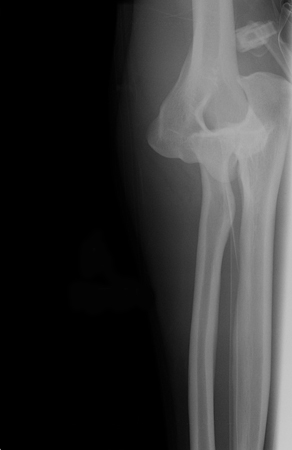

Incidência anteroposterior de radiografia de luxação do cotovelo

Acervo pessoal do Dr. Paul Novakovich